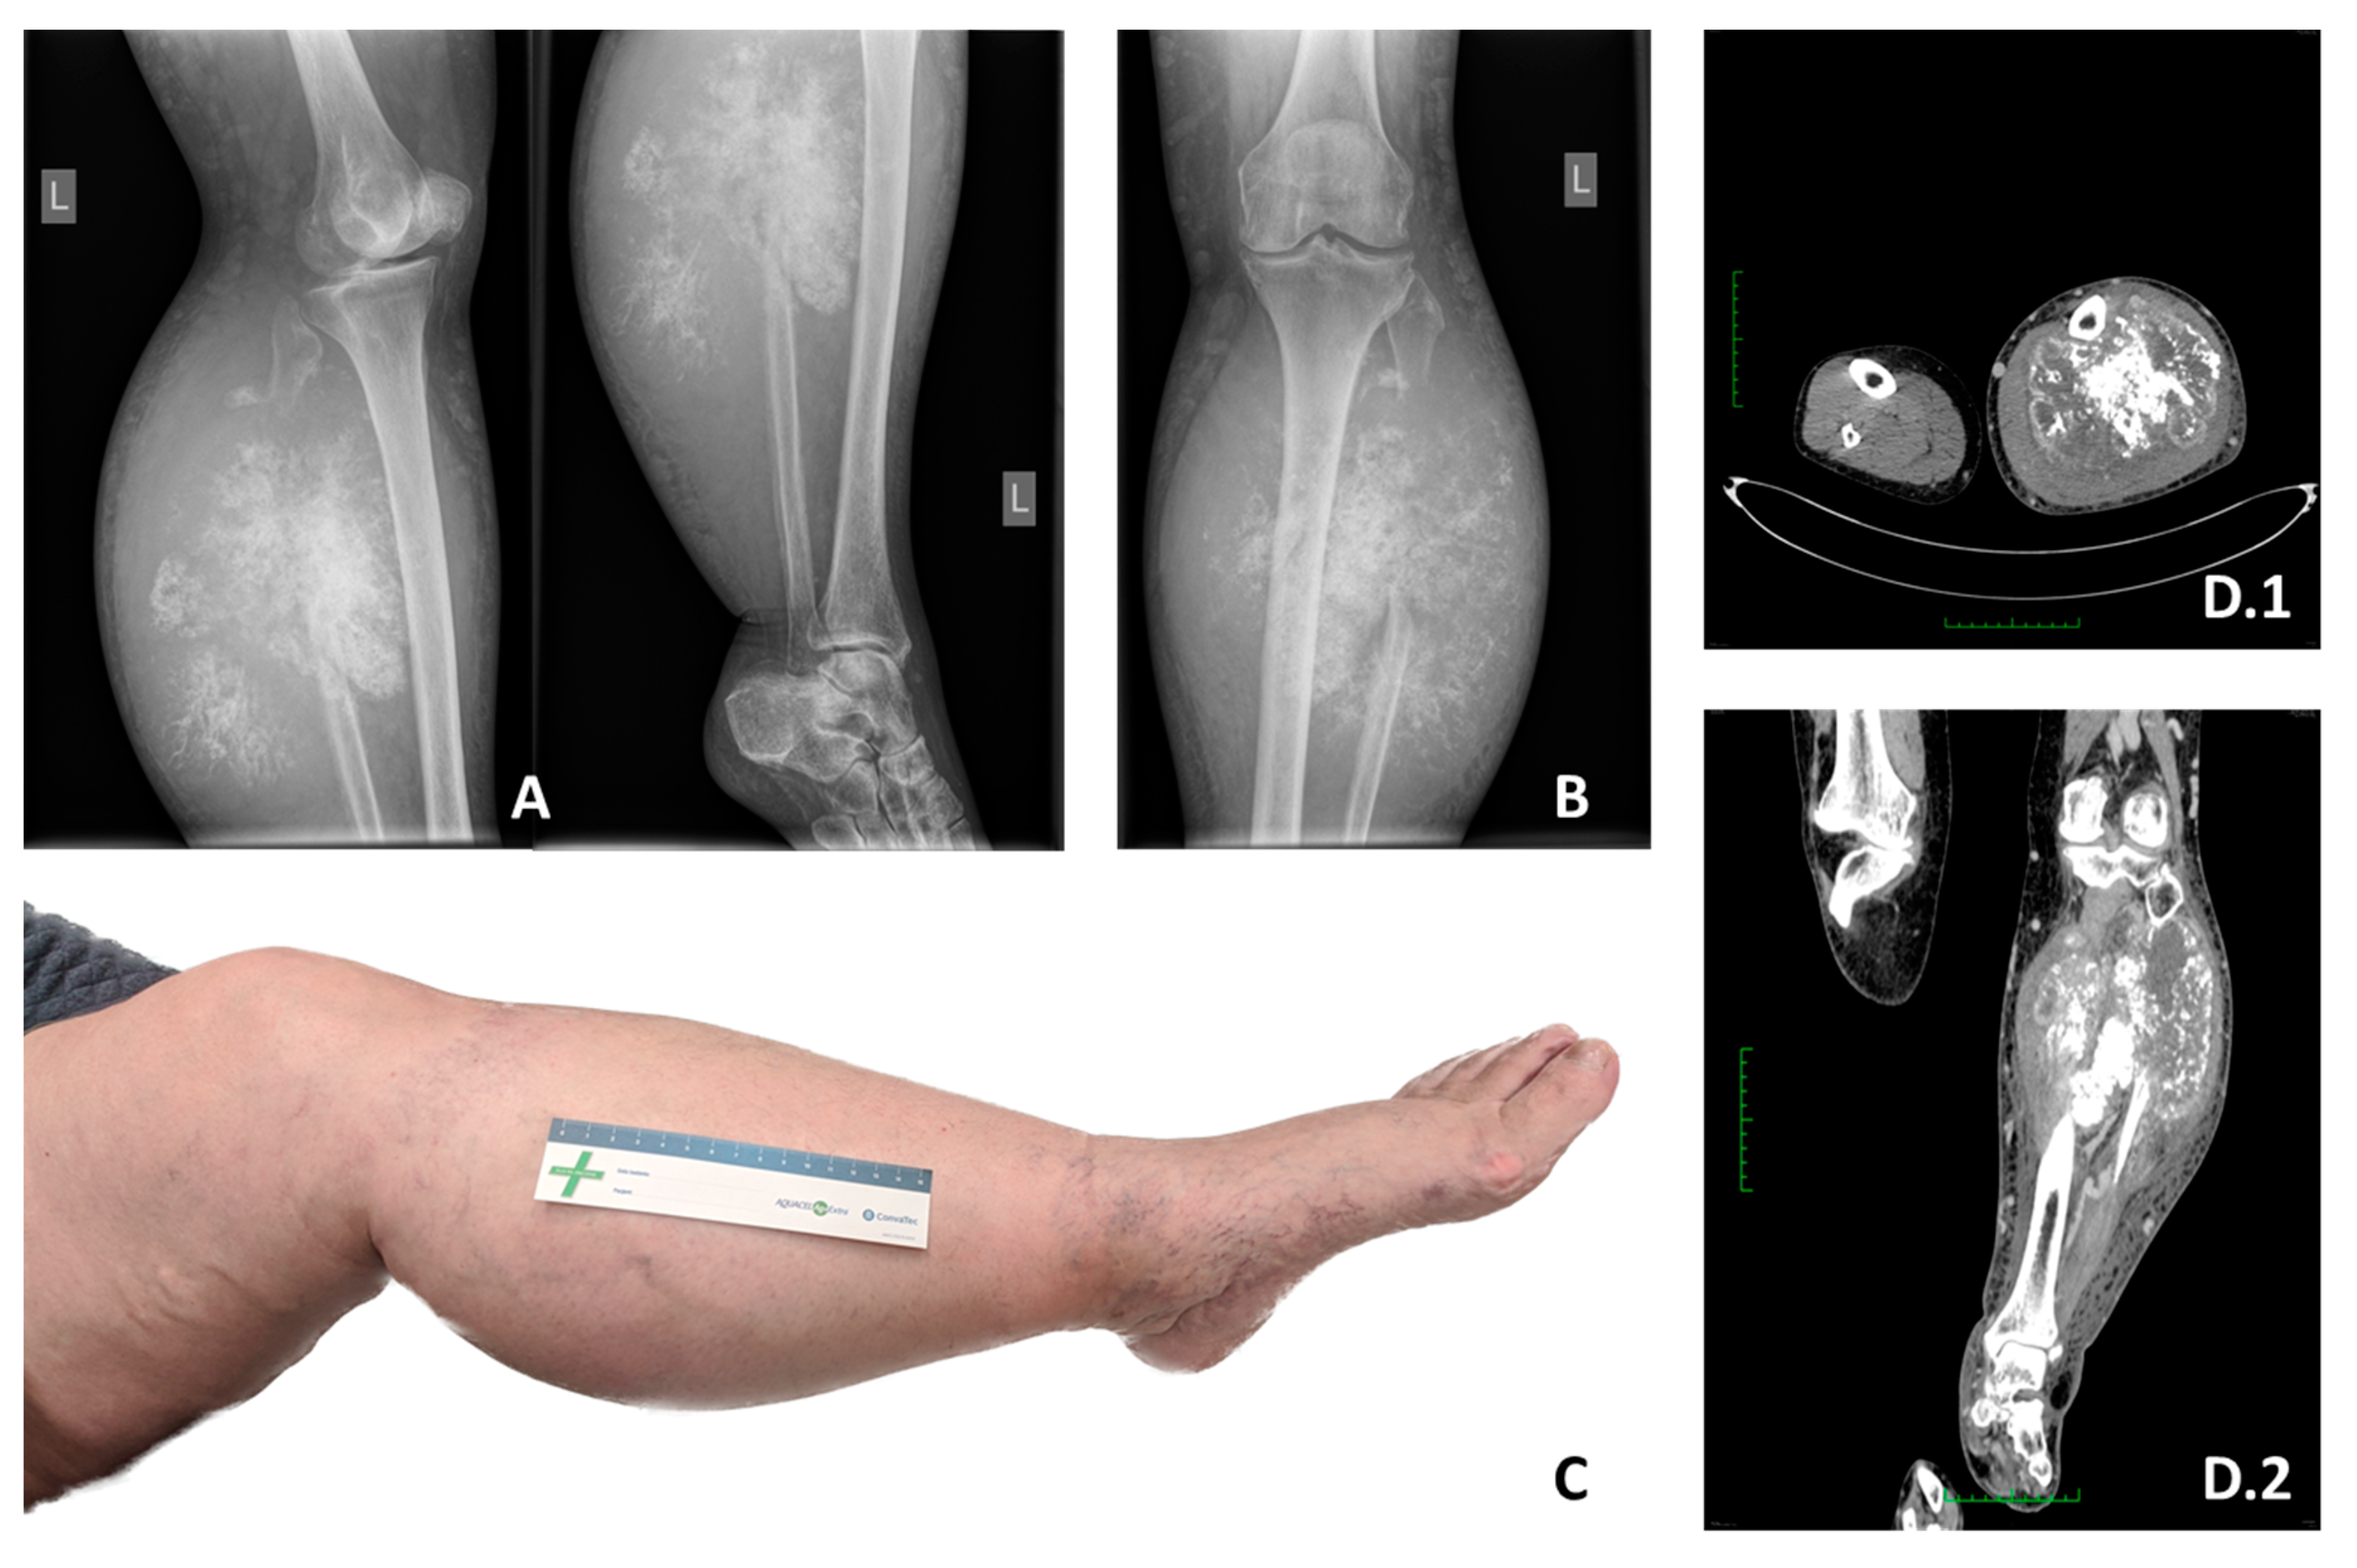

2.3. Imagining